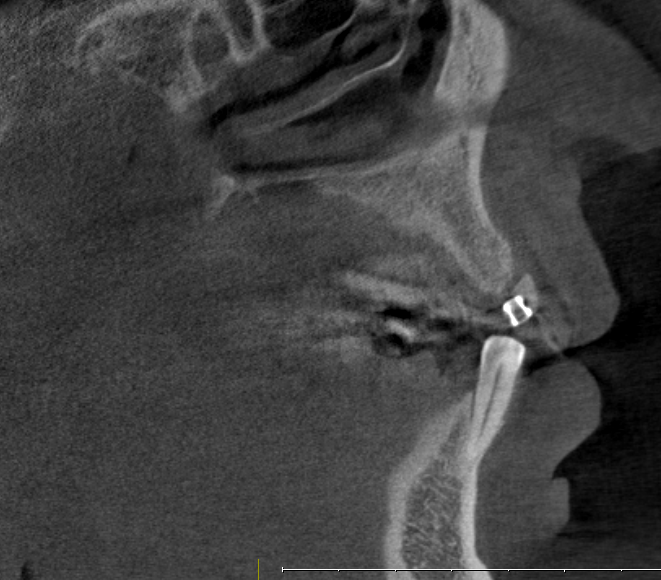

Bei nicht oder nicht vollständig durchgebrochenen Weisheitszähnen wird die darüber liegende Schleimhaut beiseite geschoben und der darüber liegende Knochen entfernt. Dann wird der Zahn mit einem Hebel entfernt. Ist dies aus anatomischen Gründen nicht im Ganzen möglich, wird das Durchtrennen des Zahnes notwendig. Das Trennen des Zahns ist obligat wenn die Platzverhältnisse keine andere Entfernungsmethode zulassen oder sich die Zahnwurzeln in unmittelbarer Nervnähe befinden. Die Wunde kann vernäht oder offen gelassen werden. Um Folgeschäden wie eine Taubheit der Unterlippe zu vermeiden kann präoperativ ein 3D DVT ( DIGITALES VOLUMENTOMOGRAMM ) zur Abklärung der Lagebeziehung von Wurzeln und Nerv sowie zur OP-Planung angefertigt werden.

Zu einer Wurzelspitzen-Entfernung wird Ihr Zahnarzt oder Kieferchirurg dann raten, wenn ein chronisch entzündlicher Prozess durch eine Wurzelbehandlung nicht behoben werden kann oder eine konventionelle Wurzelbehandlung nicht möglich ist. Auch wenn sich im Röntgenbild Veränderungen im Bereich der Wurzelspitze zeigen, die nicht eindeutig zuzuordnen sind, kann eine Wurzelspitzen-Resektion empfehlenswert sein. Um die Region der Wurzelspitzen genauer abzubilden ist es präoperativ möglich, durch ein 3D DVT (DIGITALES VOLUMENTOMOGRAMM) die Region dreidimensional abzubilden, um so eine bessere OP-Planung zu erhalten oder sich über die Frage der Erhaltungswürdigkeit des Zahns klar zu werden.

Solch ein Vorgehen erfordert allerdings auch eine möglichst exakte Diagnostik, die bei uns in der Regel dreidimensional mittels DVT erfolgt. So kann die Implantation vorher am Rechner dreidimensional simuliert werden, bevor sie am Patienten durchgeführt wird.

Kieferknochenspreizung / Dehnschrauben